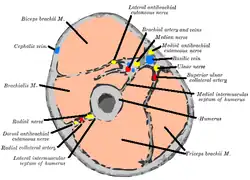

Nerves

The axillary nerve is located at the proximal end, against the shoulder girdle. Dislocation of the humerus's glenohumeral joint has the potential to injure the axillary nerve or the axillary artery. Signs and symptoms of this dislocation include a loss of the normal shoulder contour and a palpable depression under the acromion.

The radial nerve follows the humerus closely. At the midshaft of the humerus, the radial nerve travels from the posterior to the anterior aspect of the bone in the spiral groove. A fracture of the humerus in this region can result in radial nerve injury.

The ulnar nerve lies at the distal end of the humerus near the elbow. When struck, it can cause a distinct tingling sensation, and sometimes a significant amount of pain. It is sometimes popularly referred to as 'the funny bone', possibly due to this sensation (a "funny" feeling), as well as the fact that the bone's name is a homophone of 'humorous'.[4] It lies posterior to the medial epicondyle, and is easily damaged in elbow injuries.

-

Horizontal section at the middle of upper arm.

Horizontal section at the middle of upper arm. -

Horizontal section of upper arm.

-